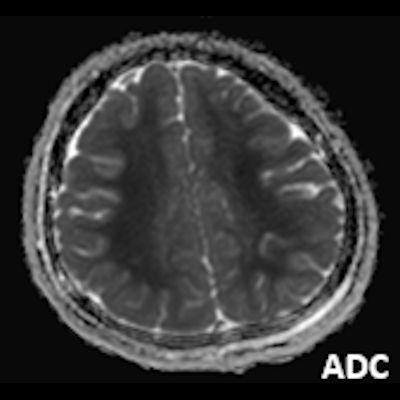

- A) Bilateral serebral kortekste (oklar) ve bazal ganglionlarda (oklar) yaygın DAG hiperintens, ADC hipointens difüzyon kısıtlamaları görülüyor.

- B) 9 gün sonraki difüzyon MR incelemede kortikal ve bazal ganglionlardaki difüzyon kısıtlamalarının gerilediği, bilateral serebral beyaz cevherde (oklar) ve internal kapsül arka bacağı- kortikospinal trakt boyunca (oklar) yaygın DAG hiperintens, ADC hipointens difüzyon kısıtlamalarının geliştiği izleniyor.